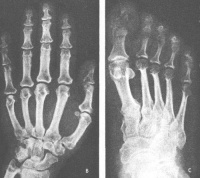

体检除上述表现外还可见心脏增大,血压增高,动脉硬化,肝脏增大,甲状腺呈弥漫性或结节性增大,基础代谢率可增高达十20%~+40%,血清蛋白结合碘大多数在正常范围内,甲状腺吸碘率也正常,故甲状腺功能大多数属正常,基础代谢率增高可能与生长激素分泌旺盛促进代谢有关。血胆固醇、游离脂肪酸常较高,血磷一般于活动期偏高,大多在4.5~5.5mg/dl之间,可能是生长激素加强肾小管对磷的重吸收所致,血钙与碱性磷酸酶常属正常。X线检查示颅骨蝶鞍扩大及指端丛毛状等病变,磁共振可显示垂体瘤的生长情况(图15-12,13)。病程较长,大多迁延十余年或二、三十年久。

(五)X线检查:头颅增大,颅骨板增厚;多数蝶鞍扩大、前后床突破坏;鼻窦增大,枕骨粗隆明显突出;四肢长骨末端骨质增生,指骨顶部呈丛毛状增生。CT扫描有助于发现微腺瘤患者。

3. 指、趾尖逐渐增大,最后形成鼓锤状。

1.形成期一般始自20~30岁,最早表现大多为手足厚大,面貌粗陋,头痛疲乏,糖尿病症群,腰背酸痛等症状,患者常诉鞋帽手套变小,必须时常更换。当症状发展明显时,有典型面貌。由于头脸部软组织增生,头皮及脸皮增粗增厚,额部多皱折,嘴唇增厚,耳鼻长大、舌大而厚、言语常模糊,音调较低沉。加以头部骨骼变化,有脸部增长,下颌增大,眼眶上嵴、前额骨、颧骨及颧骨弓均增大、突出,牙齿稀疏,有时下门齿处于上门齿前,容貌趋丑陋,如有患者前后照相作对比,变化常明显。四肢长骨,虽不能增长,但见加粗,手指足趾粗而短,手背足背厚而宽。